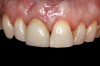

Temporization and Final Restoration

The patient was postoperatively evaluated at 1-, 2-, 4-, 8-, and 12-week recall appointments. The sutures were removed at the 2-week appointment, and the patient was instructed to rinse twice daily and avoid brushing the anterior maxilla. Prior to provisionalization of the implant, the site was allowed to heal for 6 months, during which time the patient was temporized with another Maryland bridge. At the 6-month recall appointment, full mouth periodontal maintenance was completed, and an implant-retained acrylic provisional restoration was placed (Figure 23 through Figure 25). An acrylic provisional restoration allows for soft-tissue attachment while preventing apical migration of the gingival margin. After a 3-month provisionalization period, the final prosthesis was delivered (Figure 26 through Figure 29), and the patient was scheduled for ongoing 3-month recall appointments for periodontal maintenance.

(26.) Facial and occlusal views of the soft-tissue contour achieved after 3 months of provisionalization. The tissue is thick with a harmonious gingival contour and zenith position.

Figure 26

(27.) Facial and occlusal views of the soft-tissue contour achieved after 3 months of provisionalization. The tissue is thick with a harmonious gingival contour and zenith position.

Figure 27